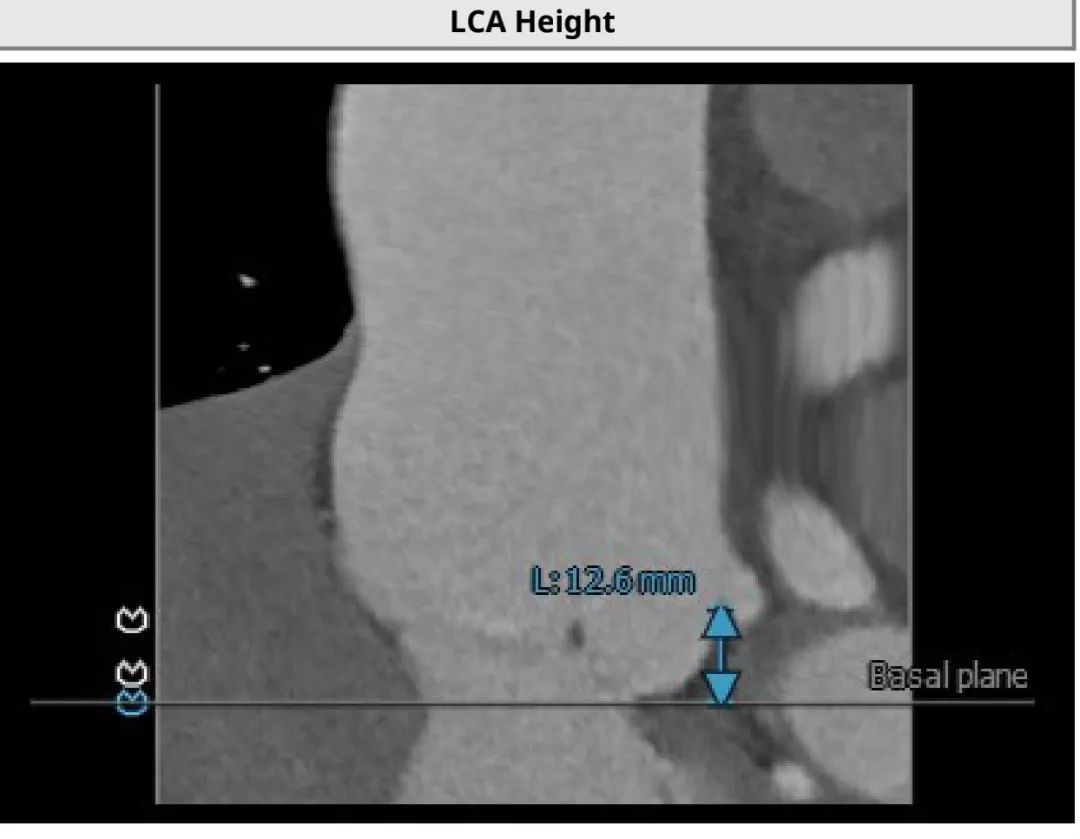

3.患者双侧冠脉开口高度可LCA:12.6mm,RCA:18.7mm;

患者左侧冠脉高度